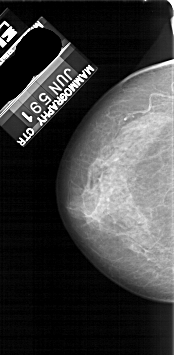

A_1118_1.RIGHT_MLO

RIGHT_MLO LINES 5281 PIXELS_PER_LINE 2611 BITS_PER_PIXEL 12 RESOLUTION 43.5 OVERLAY